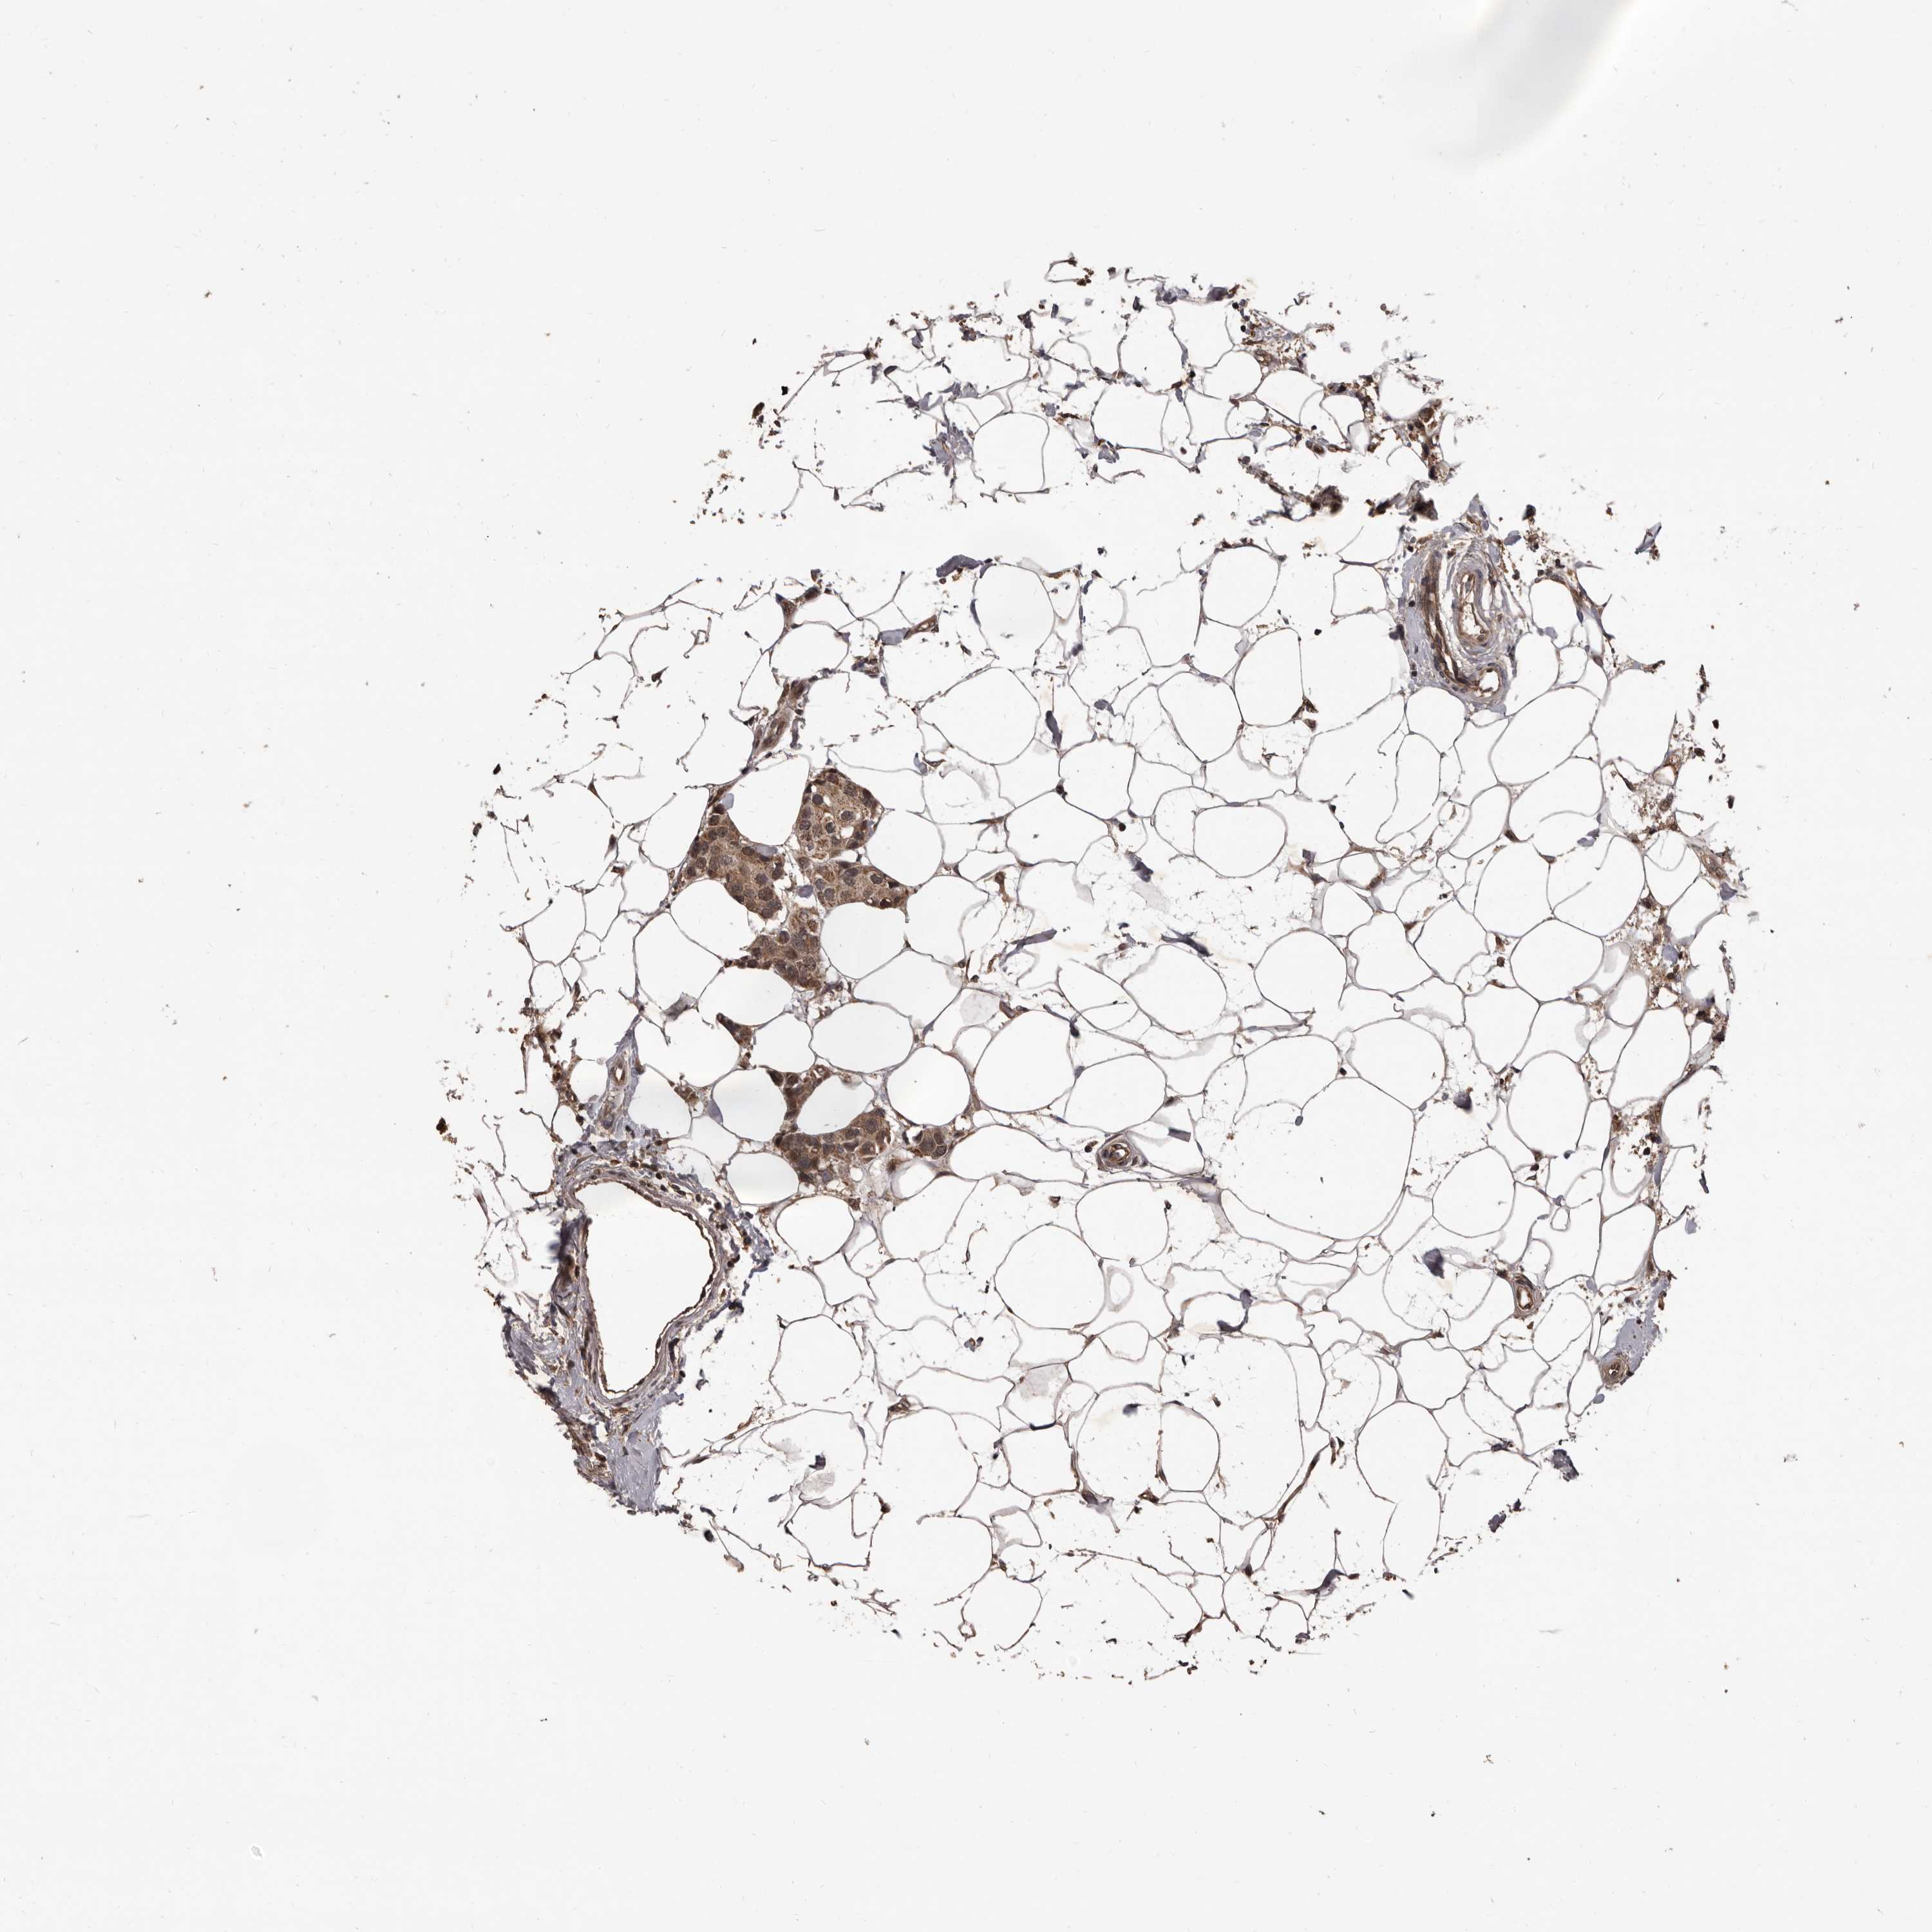

BRCA TCGA BRCA VALIDATION PROTEIN EXPRESSION